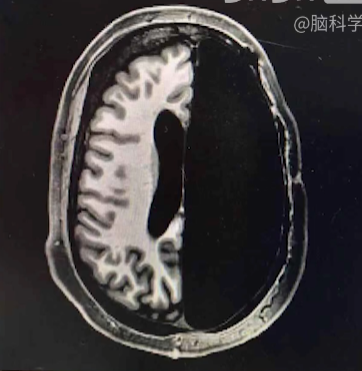

- 一个小孩因车祸摘除了一半的大脑

图2-1 - 其智力和正常人一样,但同时处理时间和空间问题时,反应会变慢

- 大脑会重新组织自己,补全失去的功能

大脑可塑性极高,会因为环境而改变